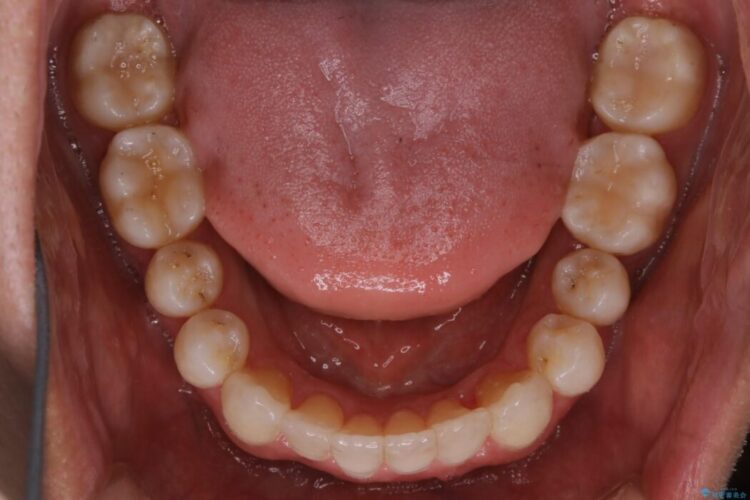

前に出ていた前歯や目立つ八重歯(3番目の歯)もきれいに並び、奥歯の虫歯治療も並行して行ったため、機能面でも見た目的にも良くなり満足していただきました。

非抜歯での矯正治療ではスペースの確保が必要となります。

本症例では上記3つの方法を複合的に組み合わせた治療を行いました。